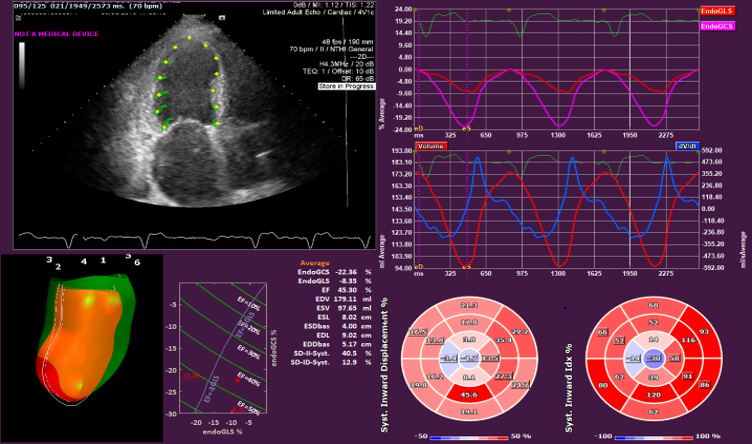

- Allows the quantitative evaluation of the Left Ventricle, Right Ventricle and the Left Atrium OEM solution. See the applications below for further details